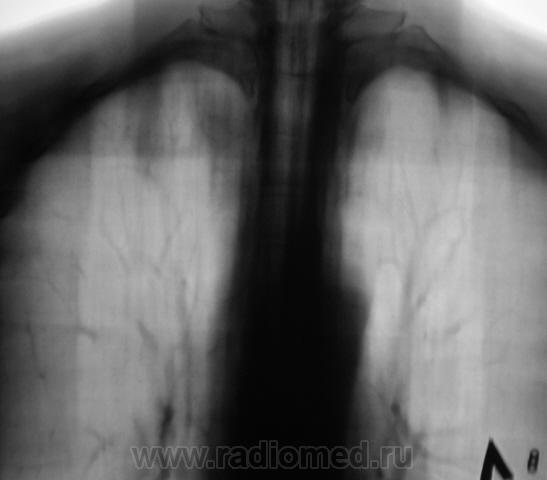

Взяли на контроль.  Какие мнения будут по поводу наличия/отсутствия специфического процесса.

Произвели стандартное дообследование.